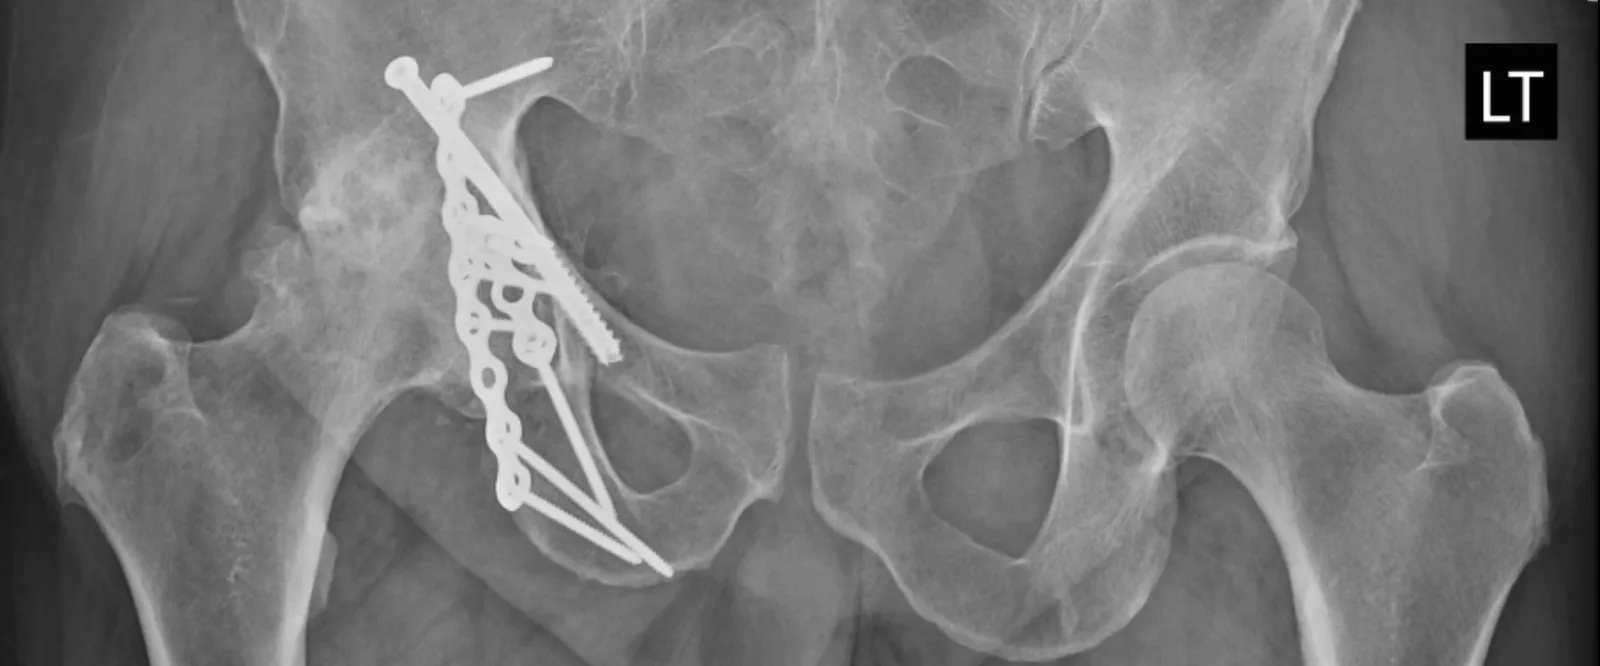

"My story started about six years ago, while playing tennis I fractured my Acetabulum in Florida. It took 10 screws, a lengthy recovery and rehab before I was able to resume my activities. However, I continued to have a level of discomfort and pain in my hip. About two years ago, the pain had gotten so severe that walking was extremely painful, I could not sit for any length of time and I found myself having to limit my activities. Both my wife and I are outdoors people, we love to hike, kayak, bike and boat; I could no longer do these things."

"The first orthopedic surgeon diagnosed my problem as arthritis that was accelerated due to my previous injury. He said that I needed hip replacement surgery but was concerned with all of the hardware that I already had in my hip, so he referred me to Dr. Denehy."